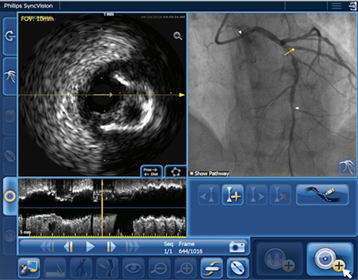

IVUS Co-registration provides easy length measurement with manual IVUS pullback and area/diameter measurements for accurate stent sizing. This feature also provides automated, real-time side-by-side display of co-registered IVUS and angio images to help correlate critical and anatomical landmarks, especially in complex cases, such as bifurcations.1,2,3,4

• Helps you understand precisely where the disease begins and ends directly on the angiogram

Obtain easy length measurements that combine IVUS and iFR information with the angiogram to help determine if a stent will meet the procedural objectives. Available on the new IntraSight system.*